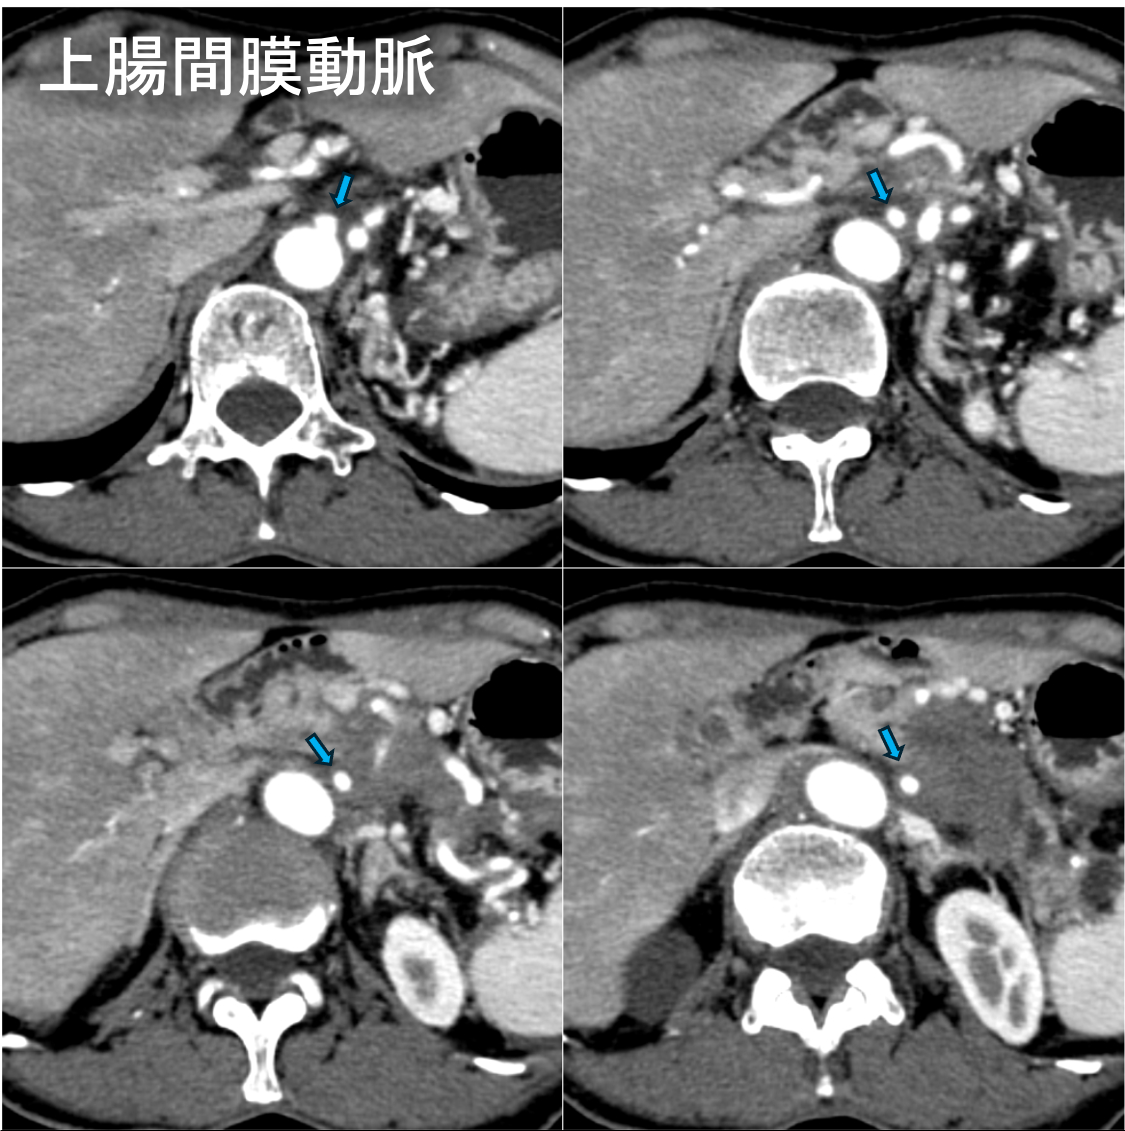

60歳台女性。心窩部痛と背部痛を主訴に来院。内視鏡を施行したところ、胃食道静脈瘤を認めたため内視鏡的静脈瘤結紮術を実施した。しかし、その後も背部痛は継続し、体重減少も出現した。腫瘍マーカーCA19-9、DUPAN-2の高値も認めたため悪性腫瘍精査目的にDynamic CTが撮影された。CTにて膵尾部腫瘍が認められた。腫瘍は腹腔動脈(CeA)、上腸間膜動脈(SMA)、門脈本幹(PV)、上腸間膜静脈(SMV)に浸潤を認めた。CTにてUnresectableと診断され、化学療法が施行された。

通常型膵癌はdesmoplastic反応すなわち間質の線維化が強く、周囲の組織を巻き込みながら成長する。また一般的に阻血に抵抗性で腫瘍内出血や壊死、脂肪変性は起こしにくい。Dynamic CTでは乏血性で浸潤性増殖を呈する腫瘍として描出され、他の膵腫瘍の鑑別に有用である。CTは、腫瘍の大きさ、周囲組織への浸潤、リンパ節転移、遠隔転移の有無などを評価できるため、腫瘍の進展度を正確に診断し、適切な治療方針を決定するための重要な情報が得られる。特に、局所における切除の可否の決定に動脈系と門脈系への浸潤の有無を評価することが重要である。膵癌取扱い規約(JPS)第7版ではUnresectable、borderline resectableに関する事項が追加され、CT診断において記載すべき重要な項目である。

最近では、低電圧CTやdual energy CT (DECT)を用いることで、造影剤の使用量を減らしつつ、低keV画像でより造影パターンを明瞭化することで腫瘍の検出率を向上させられるようになっている。抗癌剤のデリバリー効率は線維性間質量(desmoplastic反応)に影響されることから、細胞外容積分画(extracellular volume fraction:ECV) を測定することで化学療法による治療効果を予測することが可能であると報告されている(Fujitaら。EJR2023: 162)。Single energy CT (SECT)では造影前後のCT値からECVを算出していたが、DECTでは平衡相のヨード密度だけでミスレジストレーションの影響がないECV値を定量化できるとされる。